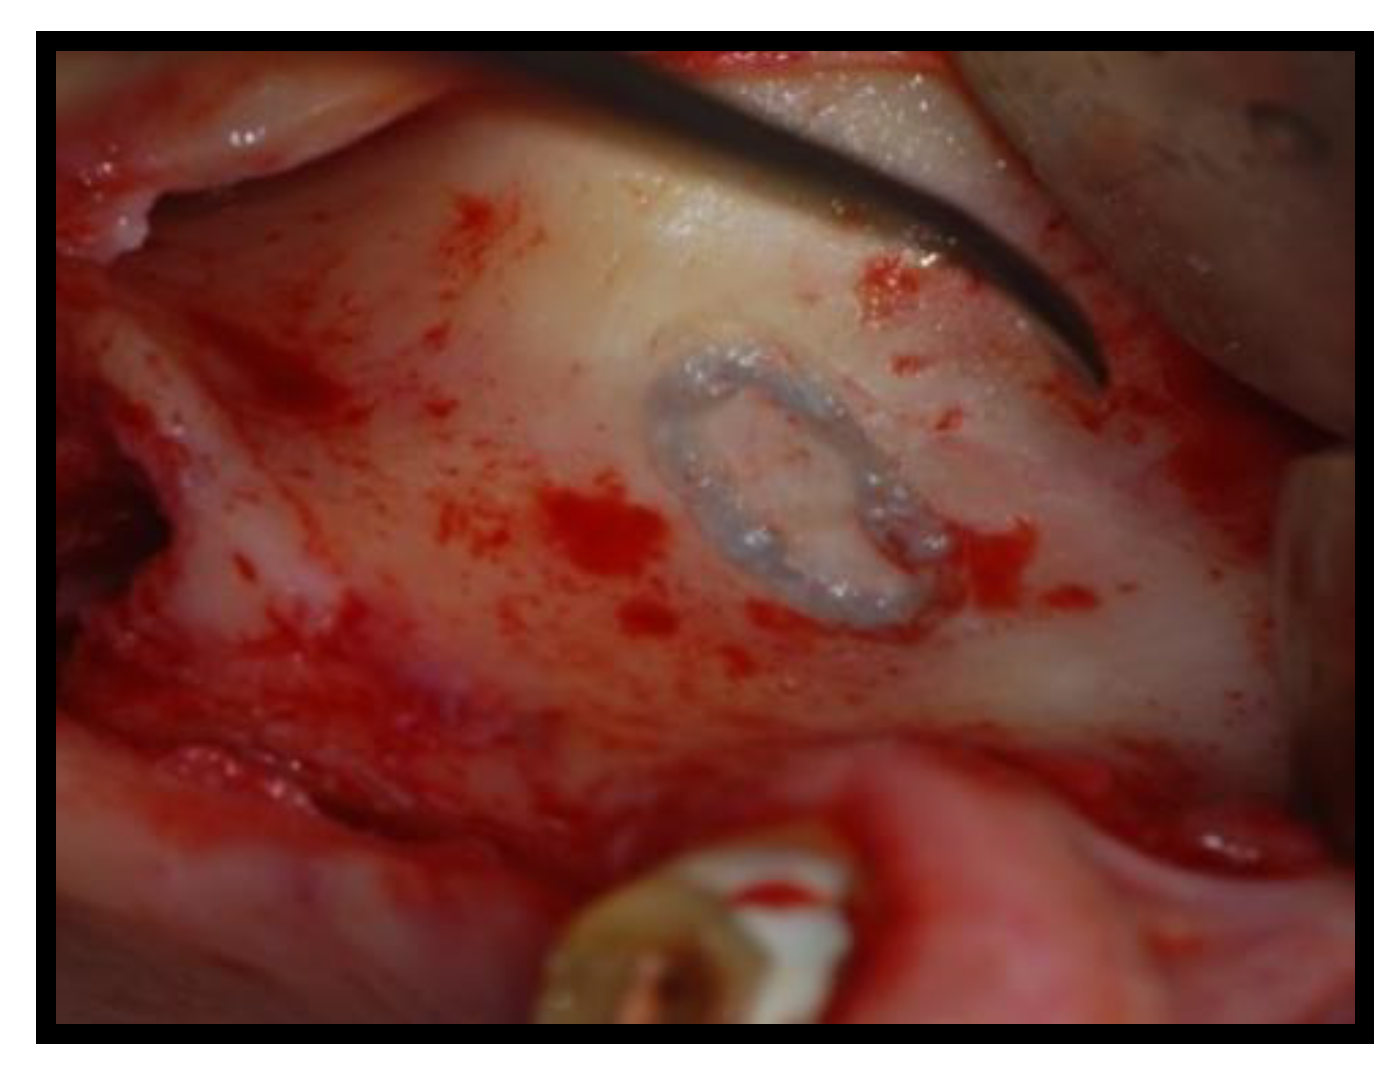

2. Materials and Methods

2.1. Surgical Procedures